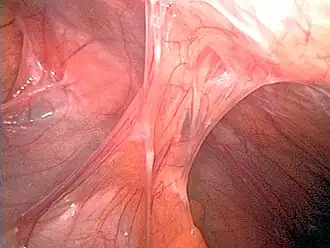

A fertilidade às vezes pode ser restaurada pela remoção das aderências, dependendo da gravidade do trauma inicial e de outros fatores individuais do paciente. A histeroscopia cirúrgica é usada para inspeção visual da cavidade uterina durante a dissecção de aderências (adesiólise). No entanto, a histeroscopia ainda não se tornou um procedimento ginecológico de rotina e apenas 15% dos ginecologistas norte-americanos realizam histeroscopia de consultório.[21] A dissecção da adesão pode ser tecnicamente difícil e deve ser realizada com cuidado para não criar novas cicatrizes e agravar ainda mais a condição. Em casos mais graves, medidas auxiliares, como a laparoscopia, são usadas em conjunto com a histeroscopia como medida de proteção contra a perfuração uterina. Microtesouras são geralmente usadas para cortar aderências. A eletrocauterização não é recomendada.[22]